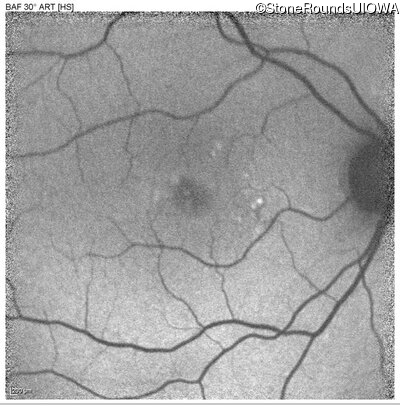

Blue Autofluorescence - Left - 20/50

Exemplar